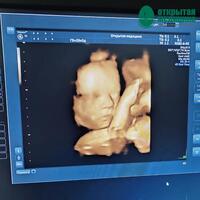

УЗИ 3D-4D отличается от обычного тем, что позволяет видеть малыша более объемно и детально. Благодаря этому получаем возможность увидеть лицо ребенка, его черты, мимику и движения. Но всё же не стоит забывать, что акушерское УЗИ – это, в первую очередь, важный медицинский инструмент, который помогает доктору оценить здоровье ребенка и своевременно выявить возможные проблемы.